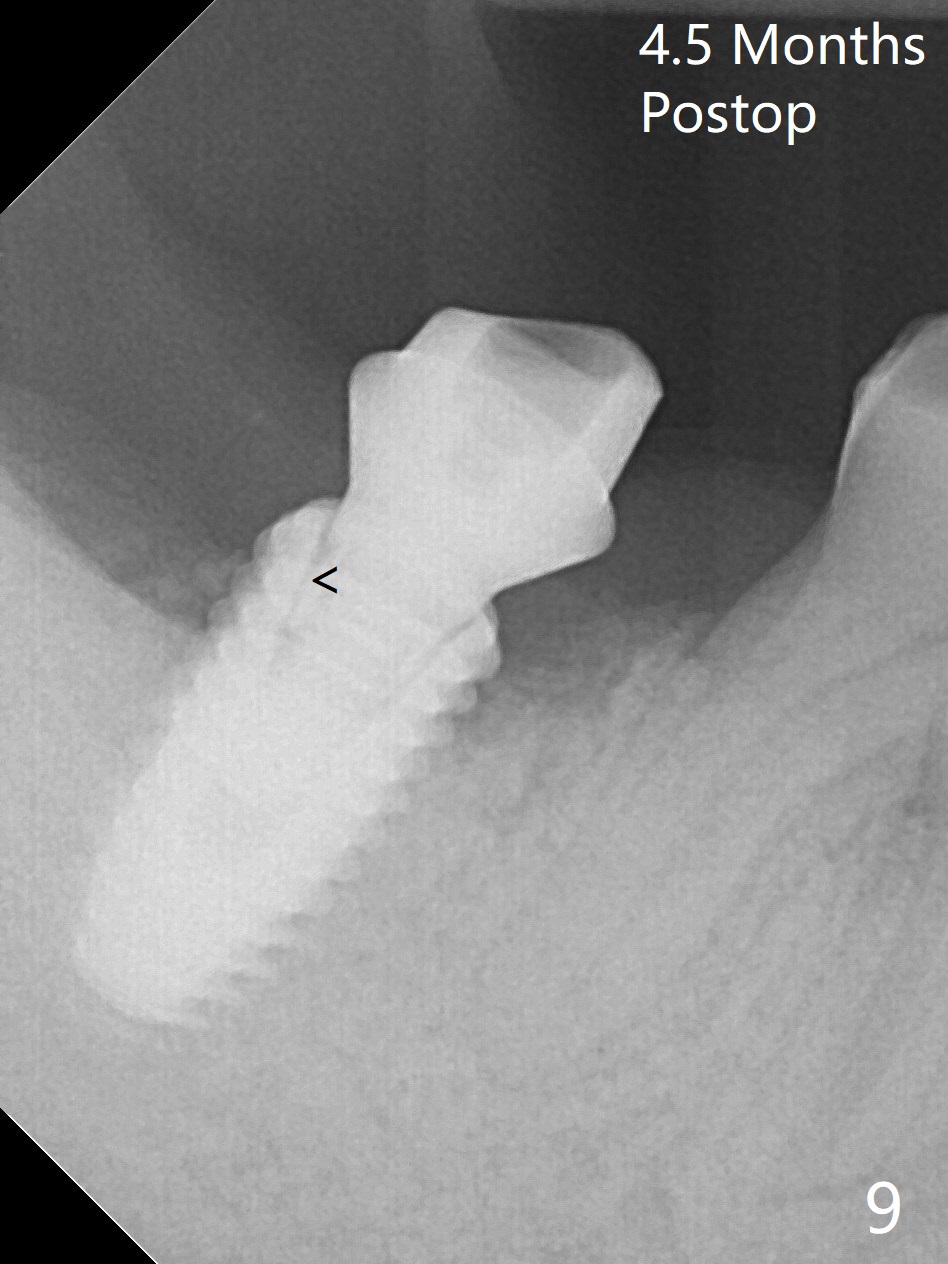

The residual roots of the tooth #31 are lower buccal (Fig.1 B), which in fact is molded and worn by the supraerupted tooth #2. When the tooth is extracted (Fig.2) and an implant, abutment (Fig.3 gold colored) and allograft (*) are placed, the abutment has to be trimmed. An atypical immediate provisional is fabricated by spreading setting acrylic over the abutment and bone graft (Fig.4 P) with occlusal equilibrium. Advantages of the guided surgery are good position (Fig.3 buccolingual), trajectory and depth (Fig.5,6) of the implant. The buccodistally exposed implant threads are packed with allograft in sufficient amount (Fig.3,5,6 *). The atypical immediate provisional breaks down and dislodges 3 weeks postop (Fig.7). In fact the implant plateau is exposed buccally. A monojet is given to the patient for self cleansing. He is instructed to return in 3 weeks. The exposed implant threads are covered 1.5 months postop (Fig.8). Incomplete abutment seating (Fig.9 <) was not noted until 1 year 3 month post cementation when the crown was mobile (Fig.10). A 6x3 mm healing abutment is placed. Three days later, the crown is sectioned and separated from the abutment. The latter returns to place; due to angulation associated with PA, the gap between the implant and abutment is indistinct (Fig.11). Bitewing is taken; the gap exists (Fig.12 <). The abutment seems to be seated deep; there is apparently soft tissue interference. A 5.2x4(2) mm abutment remains incompletely seated (Fig.13 >). A 5.2x4(3) mm one is completely seated (Fig.14 <). Zirconium crown with an access hole is cemented in the mouth. The crown and abutment is then removed for residual cement removal and reseated and torqued (Fig.15). Four months later, the Zirconium crown is fractured (Fig.16). Impression is retaken for high noble metal crown without access hole for strength (Fig.17).